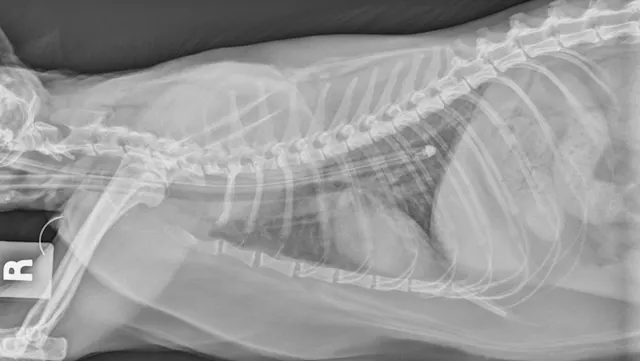

Esophagostomy tubes (E-tubes; Figure 2) are commonly used in patients with feline hepatic lipidosis. Placement requires a stable patient with corrected electrolyte abnormalities, normal cardiovascular status, and tolerance of brief general anesthesia. In the author’s experience, patients are stable for anesthesia and E-tube placement 12 to 24 hours after admission with appropriate hospitalization, treatment, and supportive care. For unstable patients, nasoesophageal or nasogastric tube placement can be considered, as these tubes are often placed without anesthesia. In the author’s experience, E-tubes allow the clinician to provide a more suitable, nonliquid diet (liquid diets often result in diarrhea) with fewer complications than with gastrostomy tubes; they also ease long-term at-home management, as owners can use the E-tube for continued enteral feeding following discharge. After the E-tube is placed, a radiograph should be obtained to ensure appropriate positioning, typically between the seventh and ninth intercostal spaces (Figure 3). Placement in the proximal esophagus may result in tube migration; placement in the stomach may result in esophageal reflux, nausea, discomfort, and vomiting.  E-tubes can remain in place as long as needed (in author’s experience, typically 3-8 weeks).

E-tube entering the left midcervical region with the patient in right lateral recumbency. The tip of the catheter can be seen exiting the oral cavity.